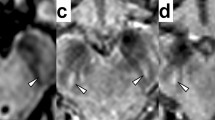

Conventional brain MRI was abnormal in all 16 (100%) neurologic origin patients, 3 (60%) hepatic origin patients, and was normal in 2 (100%) asymptomatic patients. Most of abnormalities in basal ganglia were typical symmetrical or asymmetrical hypointense on T1WI ( Figure 1a ) and hyperintense on T2WI ( Figure 1b ), with 11 patients having hypointense lesions on T2WI ( Figure 1f ). No patients showed hyperintense lesion on T1WI. While all the 17 patients with abnormal imagings have sharp margined hypointense lesions on SWI ( Figure 1 , h ).

Illustration magnetic resonance imaging and susceptibility-weighted imaging (SWI)characteristics of Wilson's disease patients. (a–d) T1WI, T2WI, SWI corrected magnetic image and corrected phase image of a 12 y old diagnosed Wilson’s disease (WD) girl; (a,b) the T1WI hypointense and T2WI hyperintense on bilateral putamen (dark arrow) and caudate, which indicate the pathological process of edema, gliosis, neuronal necrosis, or spongiform degeneration. (e–h) T1WI, T2WI, corrected magnetic image and corrected phase image of a 11-y-old, female patient; (f) nodular hypointense lesion on left putamen (white arrow), indicating paramagnetic signals; (g,h) corrected magnetic image and corrected phase image, showing marked margin of dark lesion on left putamen (white arrow).

The regions of interest were identified and hand-drawn according to the anatomical structures by a trained neuroradiologist, blinded to subject data. The value showed on the corrected phase image was the mean phase value of the structure drawn. The structures were zoomed-in by a factor of 2.0 to make the boundaries easier to define. The first, second and third slices above the AC–PC line were used to obtain data from the bilateral GP, PU, CA, TH ( Figure 4a ), and the final values were the means of the drawn. The data of the SN and RN were obtained from the slice in which the region of interest was largest ( Figure 4b ), which demonstrated the most well-defined border, and represented the expected area for each interested region. Furthermore, the slices which were severely affected by sinus artifacts were excluded.

Display of the (a) basal ganglia and (b) the midbrain of a patient with Wilson’s disease (WD), drawing 12 gray matter areas as representative regions of interest with a magnification factor of 2.0. 1, 2 = bilateral PT; 3, 4 = bilateral GP; 5, 6 = bilateral CA; 7, 8 = bilateral TH; 9, 10 = bilateral SN; 11, 12 = bilateral RN.